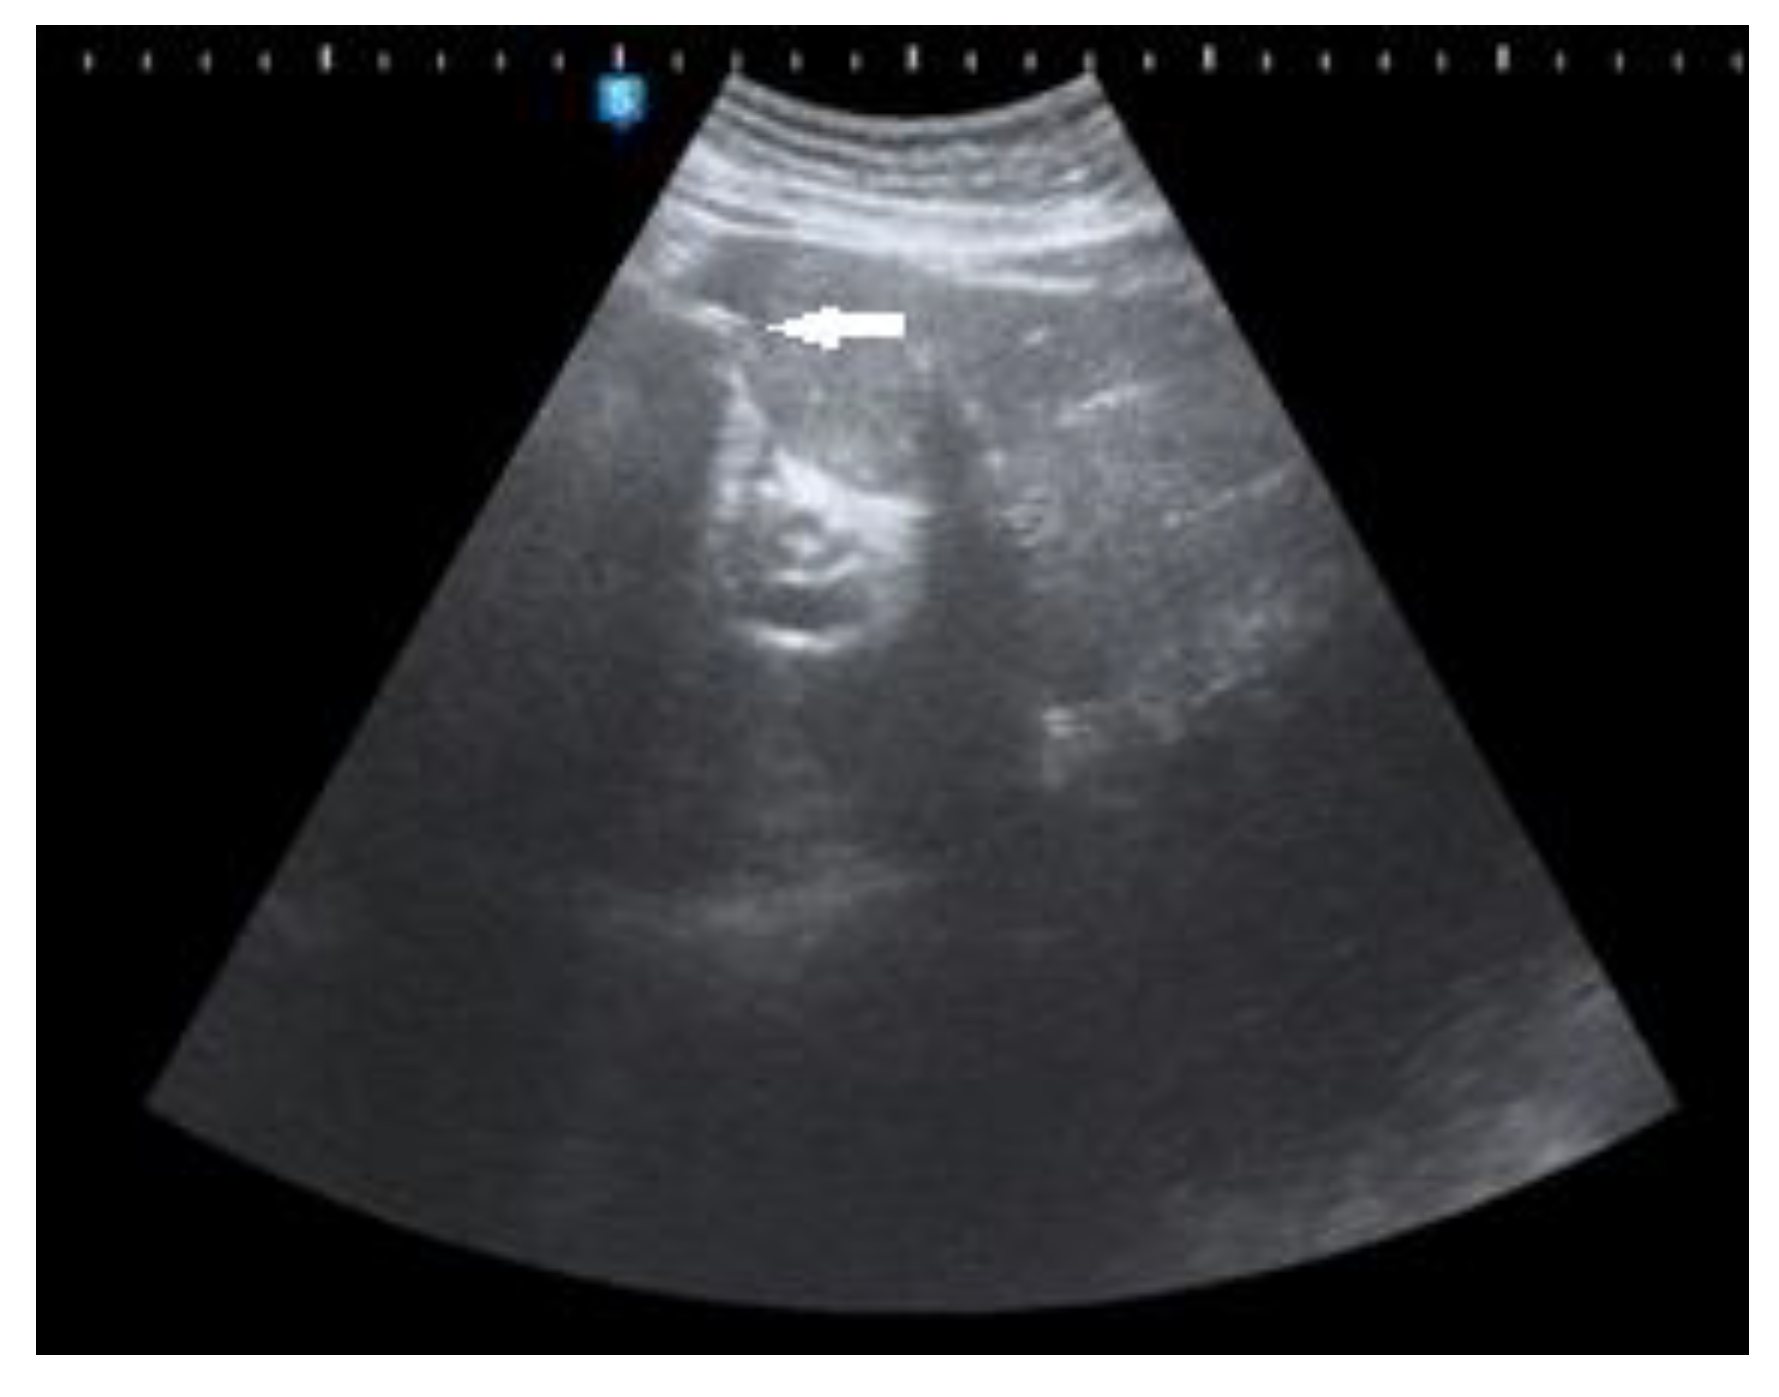

Figure 2, Figure 3 and Figure 4 Abdominal ultrasound (US) also demonstrated an enlarged stomach, a curvilinear focus of increased echogenicity with posterior shadowing in duodenal bulb which corresponds to a gallstone (long arrow) and ultrasound signs of pneumobilia. The leading diagnosis of a new finding of pneumobilia on ultrasonography with elevated white blood cell count is cholangitis. However, poor visualization of gallbladder and distended stomach can not be explained by cholangitis so CT scan has been useful as an imaging modality for diagnosis of cholecystoduodenal fistula. The other causes of pneumobilia are biliodigestive anastomosis or post-ERCP conditions.

Figure 2. Transabdominal ultrasound.